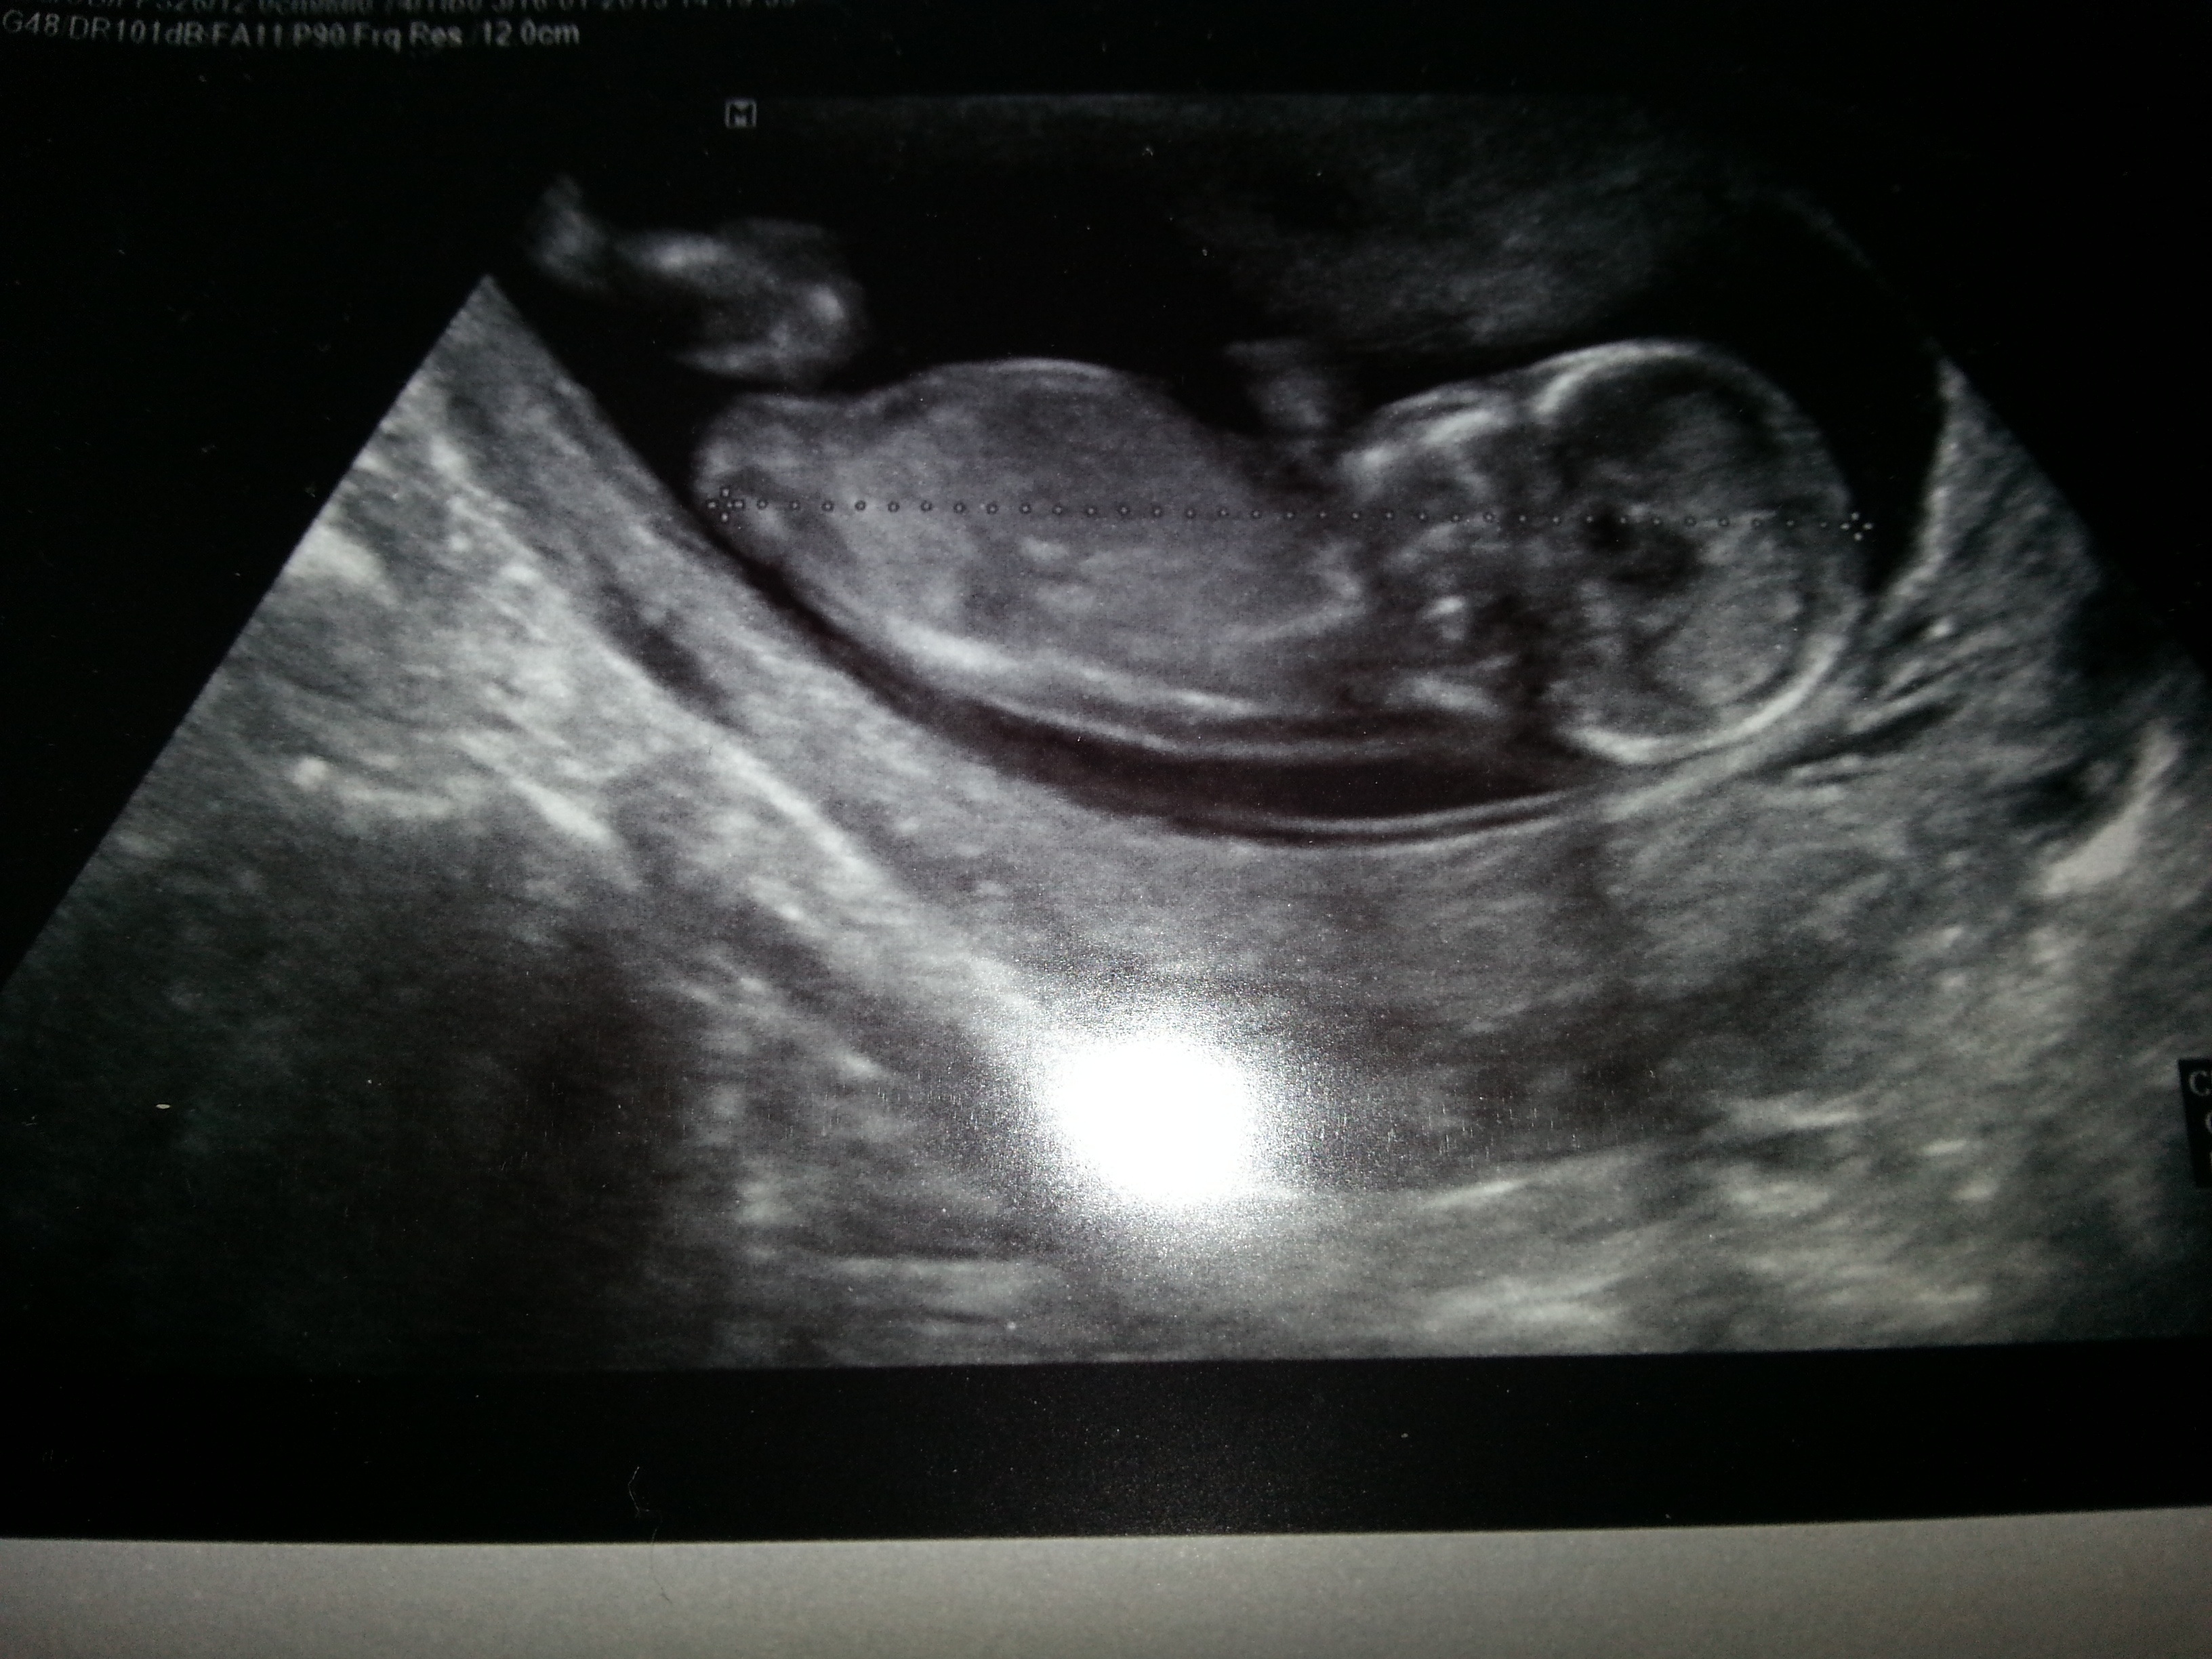

Attachment 8129

It's a little white dot/nub between babys legs, but I have no idea what it means. Do you?